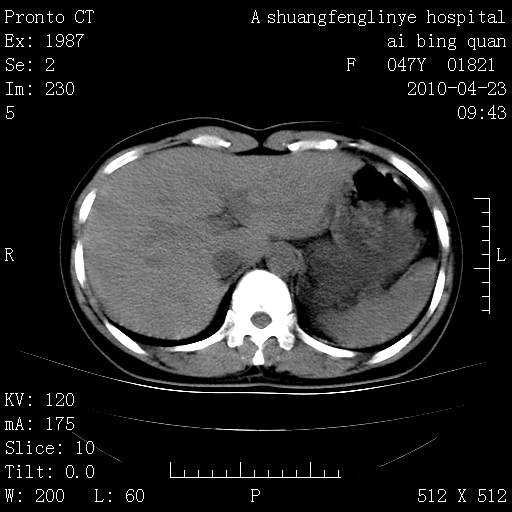

标题: CT25944:胸痛、气短、前几日高烧!肺Ca?请会诊! [打印本页]

标题: CT25944:胸痛、气短、前几日高烧!肺Ca?请会诊!

kaolv 周围型肺癌并同肺转移

双肺多发结节,考虑转移瘤,肺癌肺转移不除外

周围型肺癌并肺转移

左侧乳腺低密度灶

双肺多发结节,部分密度较高,最大结节边缘光滑。临床有“胸痛、气短、前几日高烧”病史。首选考虑:右肺感染性病变!建议积极消炎后复查!